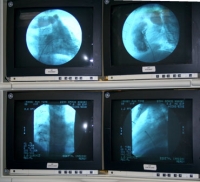

Cardiac Catheterization

A cardiac catheterization is a procedure by which a catheter (a long, thin, flexible tube) is passed into the heart to allow for more exact testing than noninvasive studies can provide. Cardiac catheterizations are performed in a hospital setting with the use of sedation or anesthesia. We offer full cardiac catheterization services at Pediatric Heart Specialists.